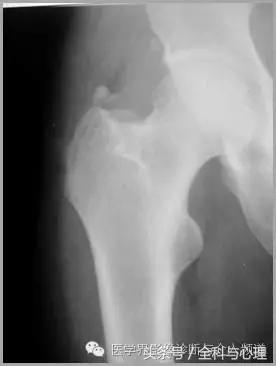

六、肌腱钙化/滑囊炎并钙化

肩关节最常见:肱二头肌长头、肩峰下滑囊钙化,可伴有急性疼痛、肿胀,局部压痛。

大粗隆滑囊炎